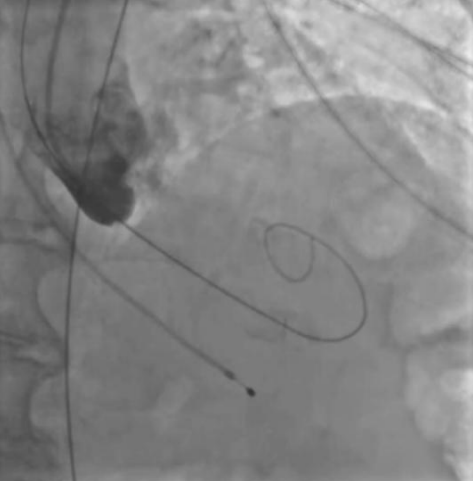

Рис. 1. Пациентка А. Ангиография корня аорты — аортальная регургитация после баллонной предилатации.

Рис. 2. Пациентка А. В момент проведения протеза визуализируется массивная аортальная регургитация.

В представленных клинических случаях по данным ЭхоКГ у всех пациенток наблюдался феномен малого объема ЛЖ (табл. 1), однако подход к проведению оперативного вмешательства различался. Так, у первой пациентки причиной неудачной ТИАК послужила сложившаяся совокупность факторов. Развившийся гемодинамический коллапс можно объяснить тем, что, вероятно, произошла объемная перегрузка ЛЖ за счет возросшей аортальной регургитации (подтверждается при выполнении аортографии (рис. 1), что в сочетании с малой полостью и диастолической дисфункцией привело к молниеносному развитию острой левожелудочковой недостаточности. В Клинических рекомендациях по ХСН (2024) подчеркивают, что у пациентов с диастолической дисфункцией и малым объемом ЛЖ риск гемодинамического коллапса значительно возрастает, особенно при наличии сопутствующей легочной гипертензии [8]. В тот момент единственным возможным решением сложившейся ситуации стало быстрое заведение и установка биопротеза. Однако даже после имплантации клапана восстановления гемодинамики не произошло. При развитии подобного сценария выполняется продвинутая сердечно-легочная реанимация (СЛР), при этом краеугольным камнем успешной СЛР у пациентов после имплантации протеза является выполнение качественных компрессий, позволяющих создать достаточное пульсовое давление, необходимое для обеспечения запирательной функции протеза и разгрузки ЛЖ. К сожалению, наличие кифосколиотического изменения грудного отдела позвоночника не позволили выполнять эффективные компрессии ни мануально, ни с помощью механического устройства для непрямого массажа сердца, вследствие чего наступившая острая левожелудочковая недостаточность не была скомпенсирована работой протеза клапана, что и привело к летальному исходу. Данные аутопсии лишь подтверждают изложенную версию произошедших событий. Также нельзя исключить влияния сопутствующей желудочковой фибрилляции и выраженной легочной гипертензии на развитие неблагополучного течения ТИАК.